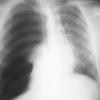

4 tension